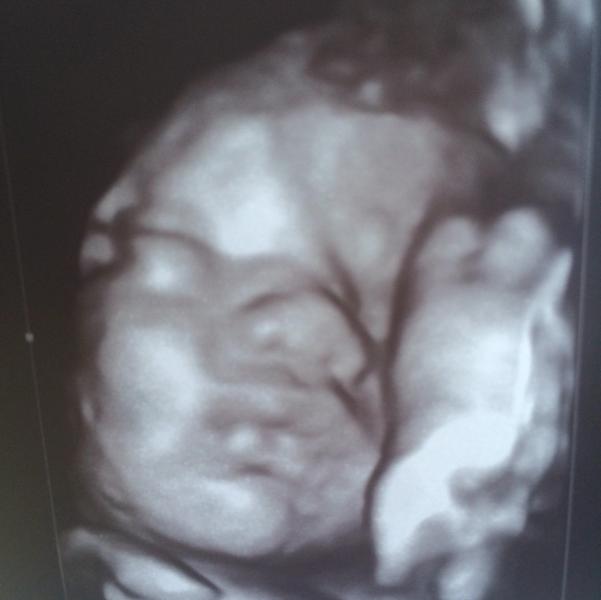

Девочки, доброе утро! А вот и мой принц😘 Вчера ходили на узи к Талько (впервые) и осталась довольной. Такая замечательная узистка👏🏼 грамотная, все разъясняет, вежливая. Записали видео, сделали фотокарточку, доплер сделали. У нас все хорошо Альхамдуллилях🙏🏼 Мой мальчик весит 2200 г, сказала крупненький и высокий (в папу) тфутфутфу 👏🏼 По последним мес нам поставили 31 нед и 6 дней, но мы выглядим на 34 недели. Говорит ли это о том что я много ем? Вроде ограничиваю себя сладкого поменьше, черный хлеб, ряженку вечером и яблоки если сильно охота есть. Отпишитесь пожалуйста кто на 31-32 неделе сколько весил? Ps. Первое что я воскликнула когда увидела его на экране "носик принца"😂 говорю большой как у папы, а у самой кнопка. Она сказала как щечки наберутся, то и нос уменьшится. Лежал гримасничал, недовольный такой, чмокал и немного ручкой помахал. Обязательно записывайте видео, девочки☺️🌹

Какой миленький, круглый носик и пухлые губки)) у него это ножка рядом с личиком?) ну и улегся)))

мы ходили к ней на 32 нед-е весили 2270 кг, все понравилось тож сказала крупненький и поставиои нам 35 недель. От того что вы кушаете это не зависит, у них в аппарате все запрограммировано и просто аппараи показывает что рост,вес и развитие на 34 недельного ребеночка идет. а так все хорошо не переживайте! фото 👍👼